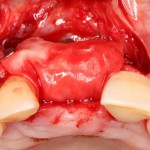

В этом случае остеопластика делается отдельной процедурой. Ее принципы точно те же, но уже без импланта. Например:

Имплантировать в таких условиях — заведомо обрекать себя на хреновый, с точки зрения эстетики и функциональности, результат. Поэтому первым этапом проводим остеопластику. Объем небольшой, использовать в таких объемах костный блок не очень рационально. Воспользуемся аутокостной стружкой и мембраной.

Сначала фиксируется BioGide. Это легко:

Затем укладывается и конфигурируется аутокостная стружка:

Если после этого BioGide намочить физраствором, им легко укрыть получившийся объем: